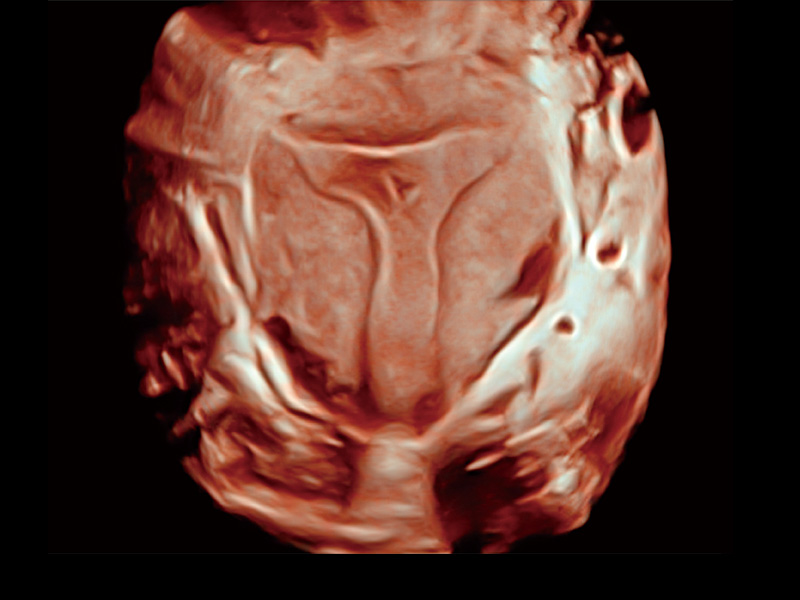

临床图

中央型宫腔粘连